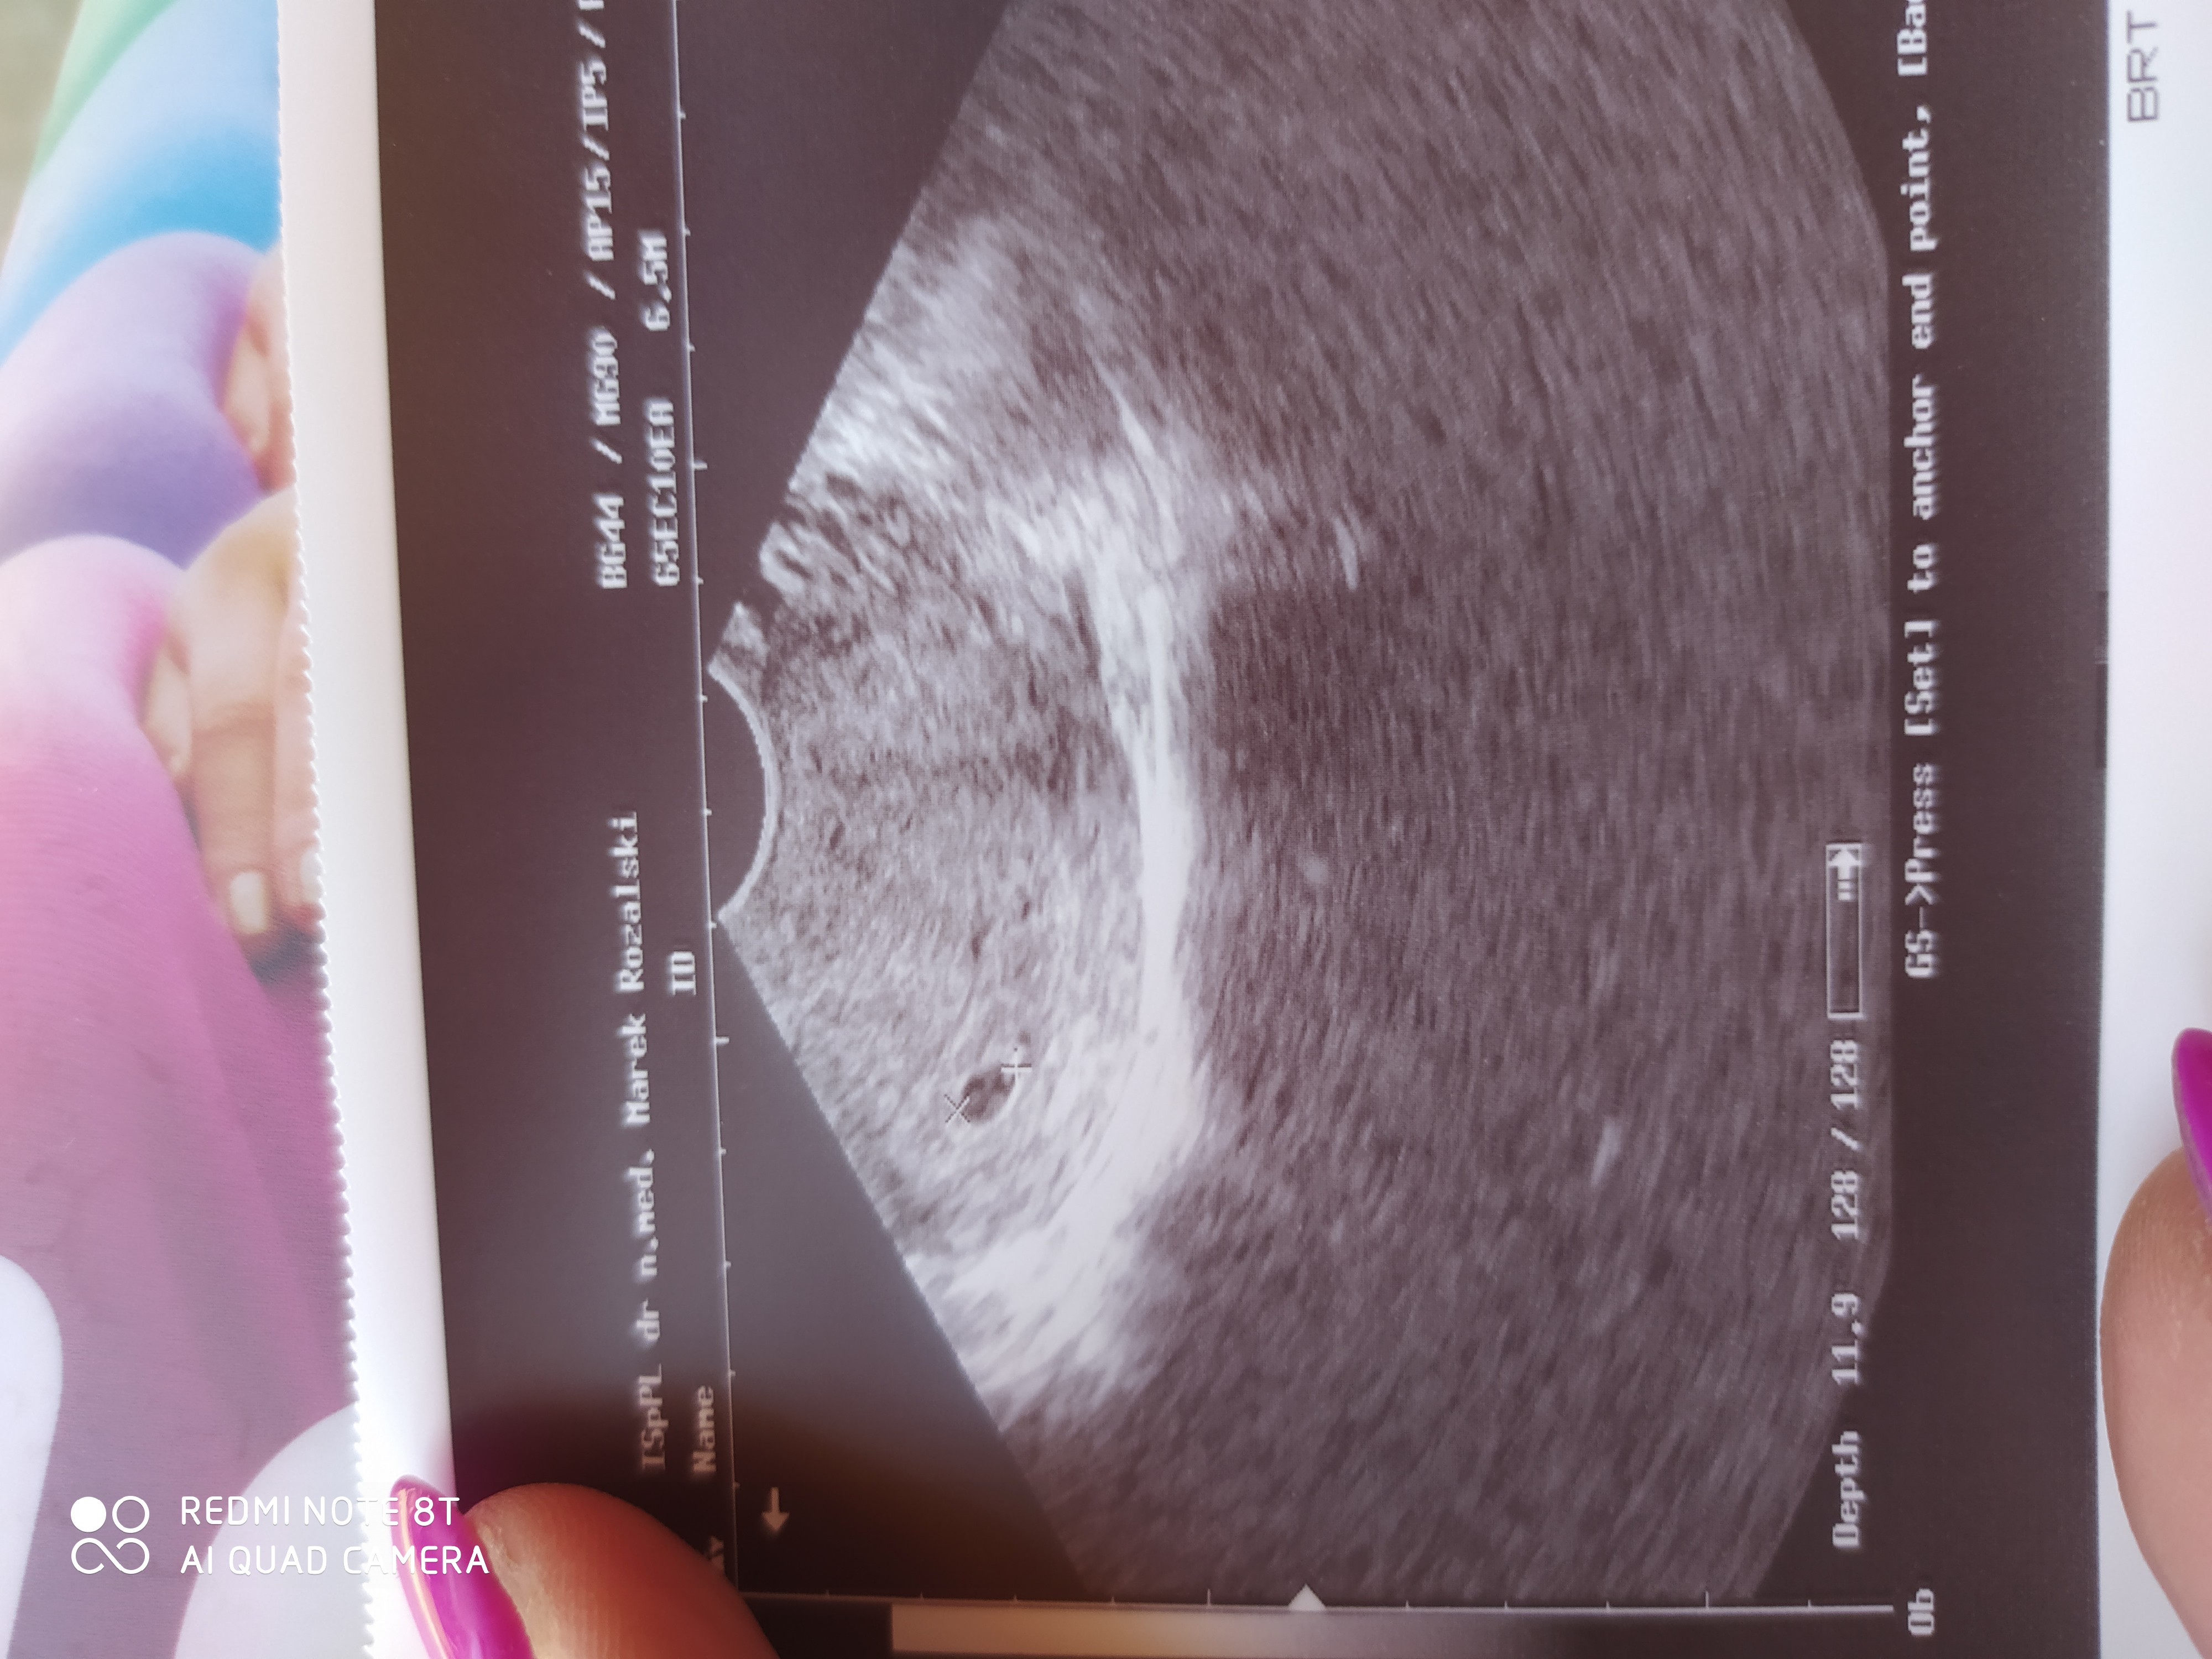

Witam dziewczyny. Byłam dziś na pierwszej wizycie in mam swoją kropeczke 5 tydzień kolejna wizyta za 3 tyg. PozdrawiamZobacz załącznik 1142163Zobacz załącznik 1142163Zobacz załącznik 1142163

GratkiWitam dziewczyny. Byłam dziś na pierwszej wizycie in mam swoją kropeczke 5 tydzień kolejna wizyta za 3 tyg. PozdrawiamZobacz załącznik 1142163Zobacz załącznik 1142163Zobacz załącznik 1142163

GratulujeWitam dziewczyny. Byłam dziś na pierwszej wizycie in mam swoją kropeczke 5 tydzień kolejna wizyta za 3 tyg. PozdrawiamZobacz załącznik 1142163Zobacz załącznik 1142163Zobacz załącznik 1142163